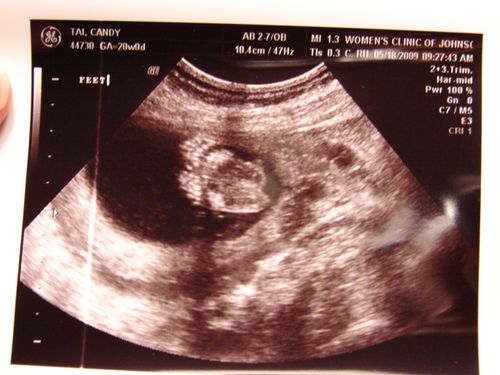

My little baby boy is looking healthy and growing so fast! His approximate weight is 13.5 ounces and he is quite flexible – at one point during the sonogram, he was seen tapping his foot on top of his little head! Nathan and Will got quite a kick out of that. The sonographer was very nice and even printed each of them their very own personalized photo that read "Hi Nathan" and "Hi William", complete with a great view of baby's head.

Feet!